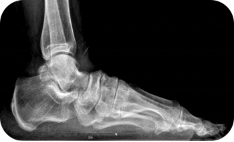

X线测量法:第一跖骨距骨角、距舟覆盖角及跟骨倾斜角等参数的测量,对足进行影像学评估

足负重前后位、足负重侧位(足内弓角测量、外弓角测量、跟骨倾斜角)